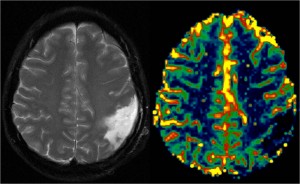

Il team di ricercatori della QMRI Tech è esperto di studi di neuroimaging mediante tecniche RM di Perfusione con mezzo di contrasto (DSC e DCE MRI), Diffusione (DWI e DTI), IVIM, Spettroscopia, fMRI Bold, Rilassometria, Texture Analysis.